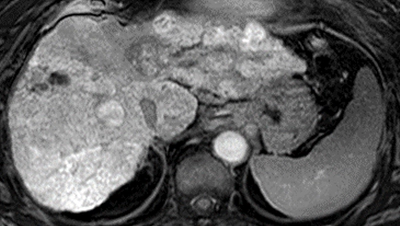

肝動脈化学塞栓療法と薬剤2種の併用で肝細胞がんへの治療効果が向上 レンバチニブとペムブロリズマブ併用による肝細胞がんの完治に期待

肝細胞がん免疫療法の効果を予測する画像バイオマーカーを発見 免疫療法の効果がない患者に対するMRI診断の有効性を証明